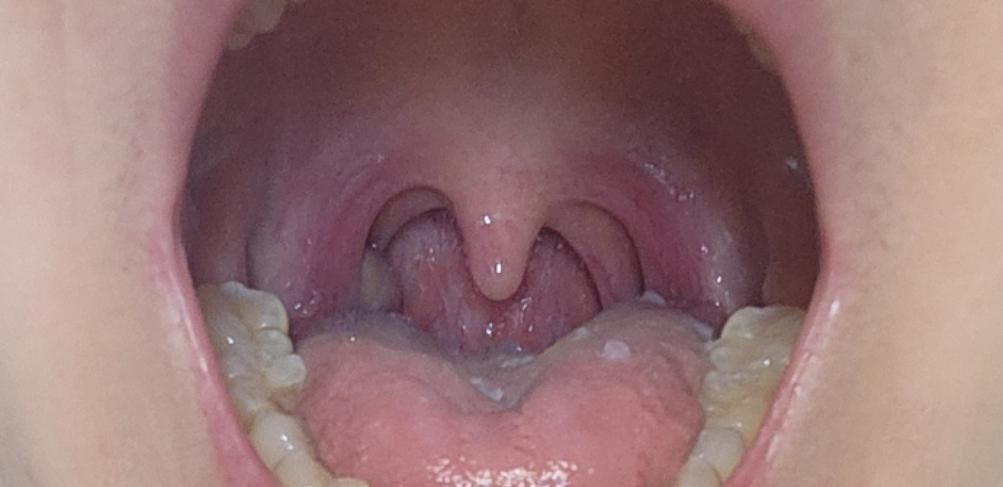

감기로 목이 부은거 같은데 옆에 노란게 있어요

오른쪽 편도에 노란부분이 무엇일까 궁금해요?

그전에는 찍어본적이 없어서 모르겠어요.

40대 여성분의 감기 증상과 함께 오른쪽 편도에 노란 부분이 보이는 것에 대해 걱정이 많으시겠어요. 편도에 보이는 노란색은 종종 편도결석일 수 있으며, 이는 음식물 찌꺼기나 세균이 뭉쳐져 생기는 현상일 수 있습니다. 하지만, 감기 증상과 함께 나타나는 경우 편도염으로 인한 고름일 가능성도 배제할 수 없으니 정확한 감별을 위해 이비인후과 진료를 받아보시는 것이 좋겠습니다.

편도결석은 심각한 질환은 아니지만, 입 냄새를 유발하거나 이물감을 줄 수 있습니다. 불편함이 심하다면 제거를 고려해 볼 수 있습니다. 하지만, 편도염으로 인한 고름이라면 항생제 치료가 필요할 수 있으므로, 꼭 병원에 방문하셔서 적절한 치료를 받으시길 바랍니다. 건강을 기원합니다!